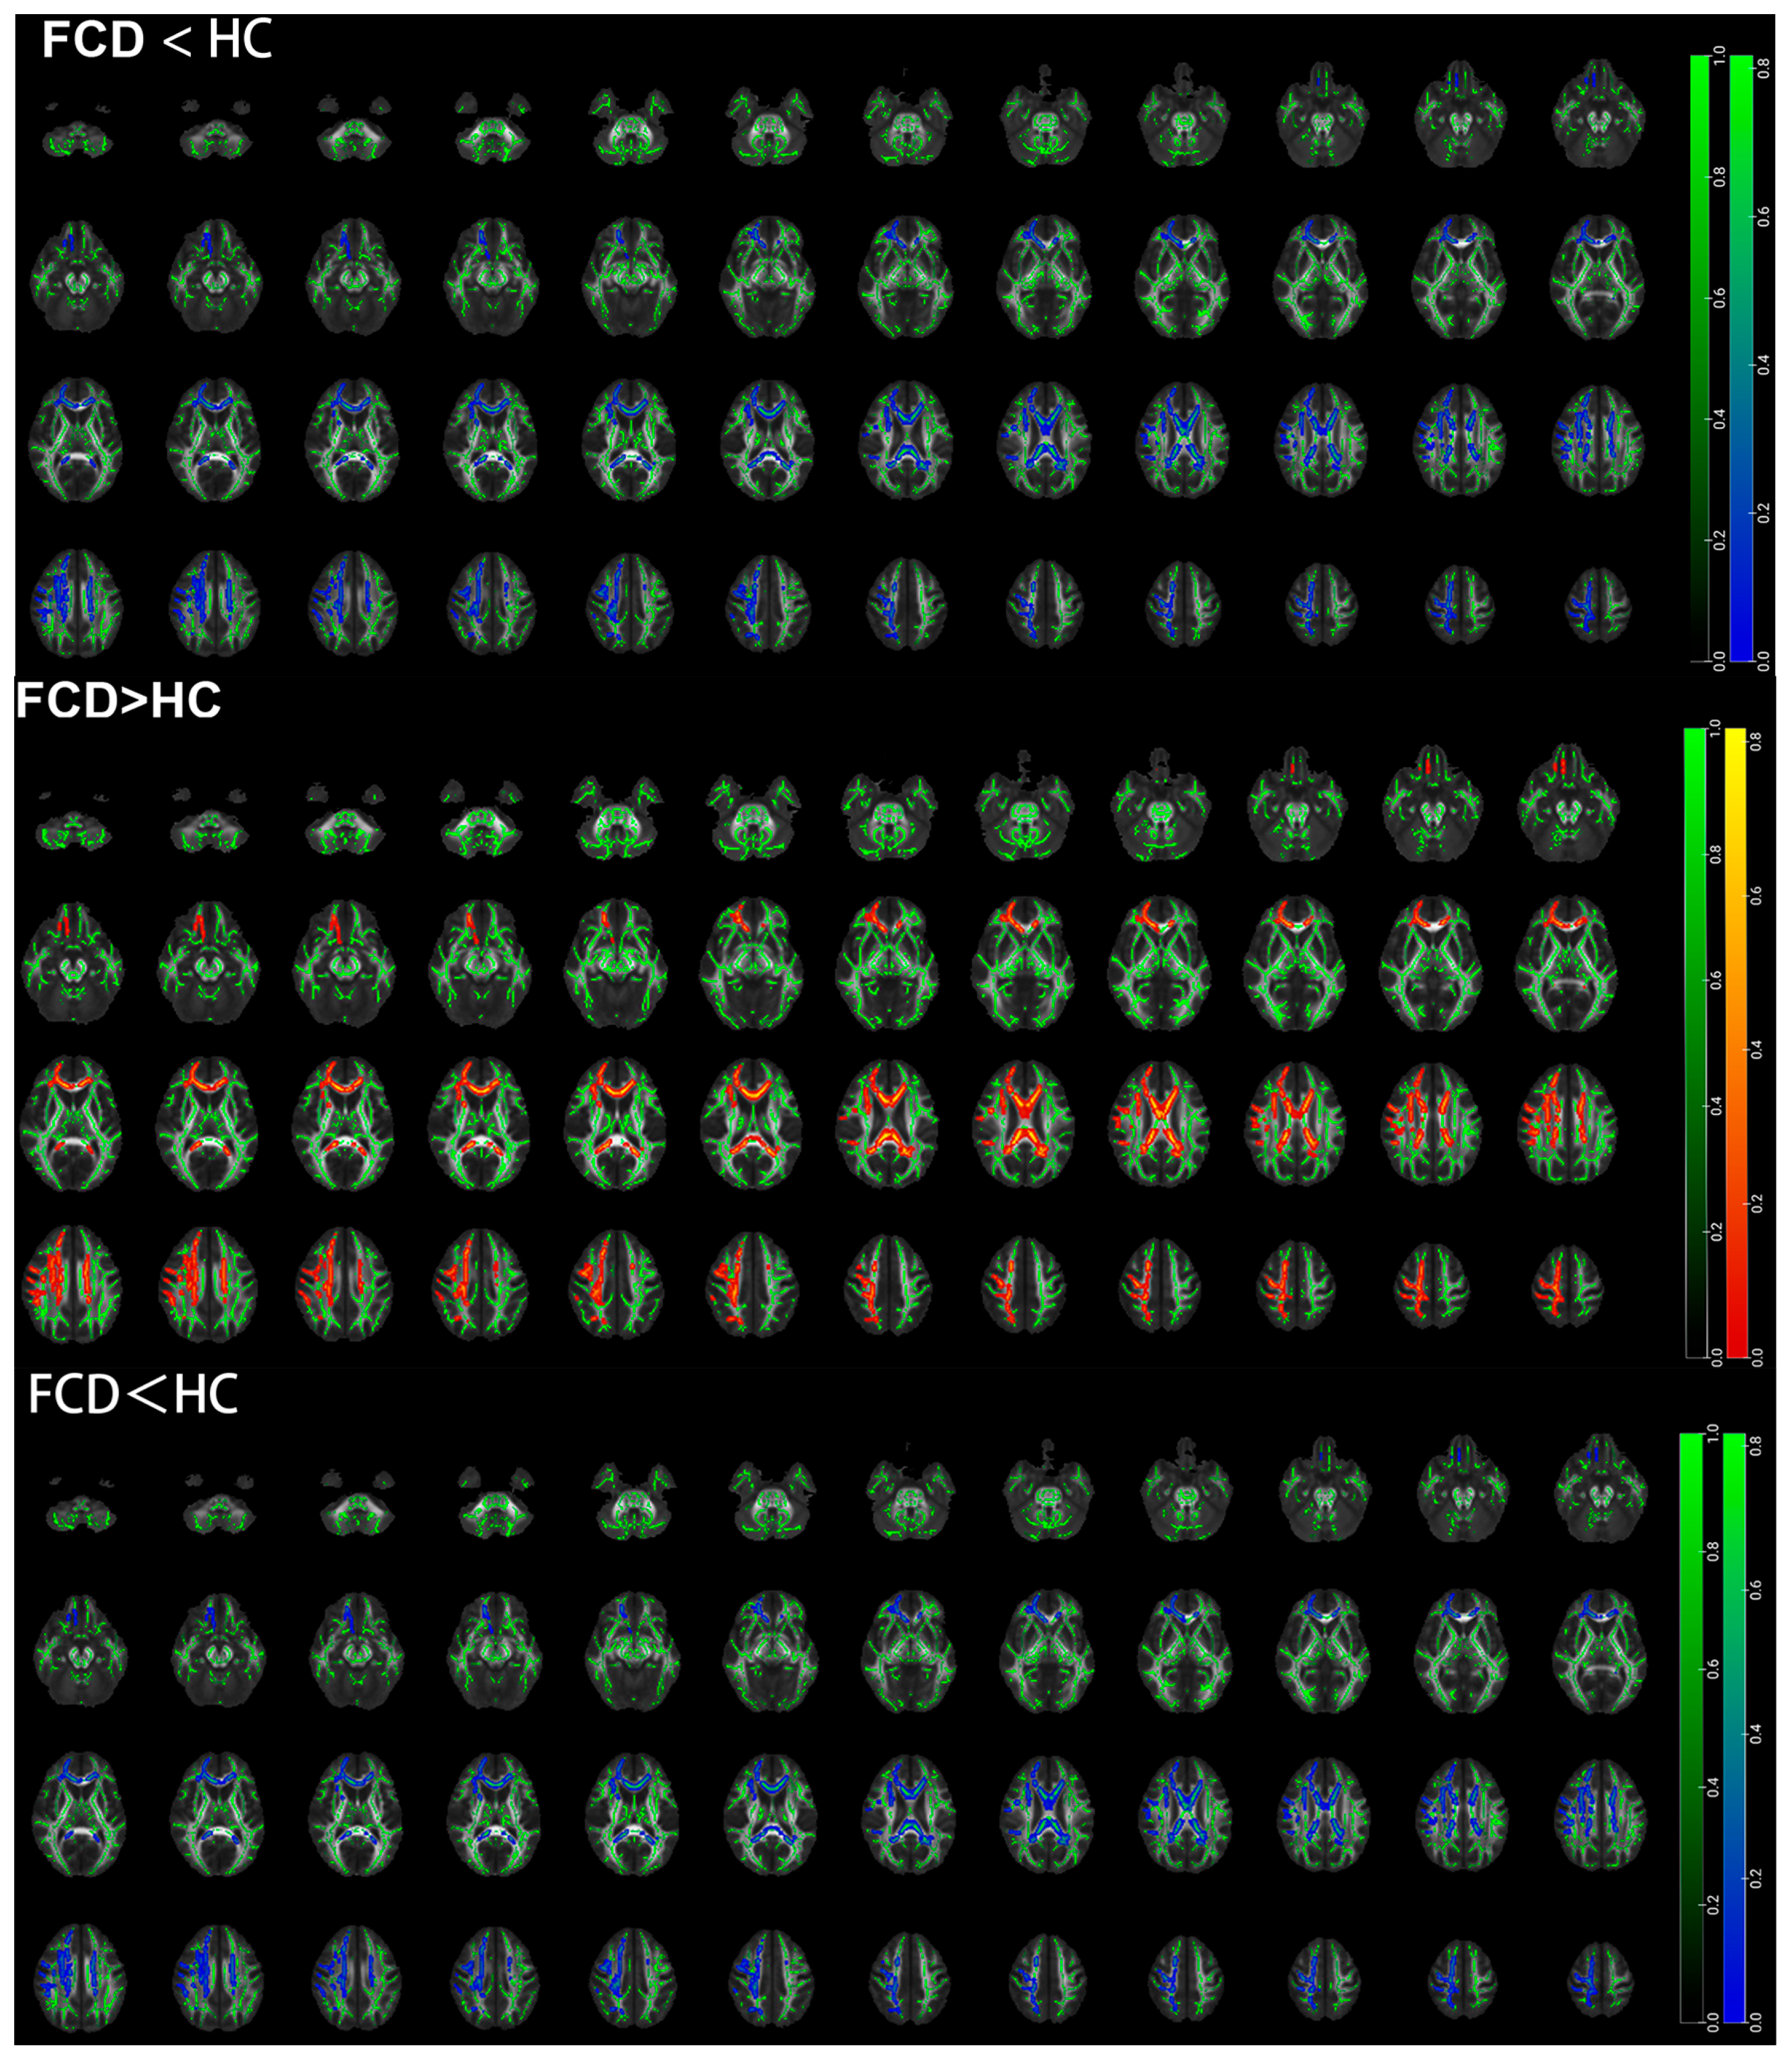

3.4. TBSS Results Based on the Whole Brain of Pediatric FCD Patients

| FCD < HC | ||||||

| Middle cerebellar peduncle | 115 | 24.3 | −60.4 | −38.8 | 0.965 | |

| Cingulum (cingulate gyrus) | L | 50 | −7.46 | 19.7 | 25.1 | 0.971 |

| Superior corona radiata | L | 10 | −28.4 | −0.197 | 19.2 | 0.971 |

| FCD > HC | ||||||

| Middle cerebellar peduncle | 95 | −12.2 | −22.1 | −28.4 | 2.1 | |

| Internal capsule | R | 75 | 36.2 | −37 | 8.62 | 1.98 |

| Posterior thalamic radiation | R | 57 | 35.2 | −55.6 | 0.364 | 1.82 |

| Medial lemniscus | L | 42 | −4.15 | −34.8 | −40.3 | 2.43 |

| External capsule | L | 34 | 35.5 | −56.9 | 13.7 | 1.87 |

| Superior longitudinal fasciculus | R | 26 | 40.7 | −40.8 | 17 | 1.54 |

| Cerebral peduncle | L | 25 | −11.2 | −26.5 | −17.8 | 2.12 |

| Posterior thalamic radiation | L | 25 | −31.2 | −67 | 7.41 | 2.22 |

| Medial lemniscus | R | 16 | 4.51 | −37.1 | −34.9 | 1.92 |

| Superior corona radiata | R | 15 | 27.4 | −23.2 | 33.2 | 2.06 |

| Fornix | L | 14 | −25.7 | −33.2 | 7.25 | 1.98 |

| External capsule | R | 11 | 35.1 | −2.74 | −11.6 | 1.67 |

| Superior corona radiata | L | 10 | −21 | −14.6 | 35.5 | 1.37 |

| Superior longitudinal fasciculus | L | 10 | −35.9 | 0.816 | 26 | 1.4 |

| Cingulum (cingulate gyrus) | L | 10 | −6.44 | −9.68 | 35.9 | 1.8 |